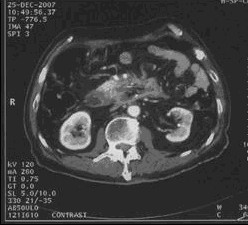

男,68歲,2006年12月14日,CT掃描發(fā)現(xiàn)胰頭占位性病變,6.0×4.7cm2,腹膜后淋巴結(jié)轉(zhuǎn)移,伴肝內(nèi)多發(fā)轉(zhuǎn)移灶。艾恒+希羅達(dá)化療3療程無效(圖1)。2007年4月5日,開始接受今又生治療,胰腺腫瘤內(nèi)注射今又生1×1012VP,共2次,結(jié)合放療45Gy/10f(圖2)。2007年5月12日,IMA64+C,5.3×3.5=18.6cm2,縮小41.0%,瘤囊性化。腹腔灌注今又生5次,1-2×1012VP/次/周,+順鉑60mg,健擇每周1.4g,治療2周。療后1年,腫瘤進(jìn)一步縮小及壞死(圖3)。

治療中